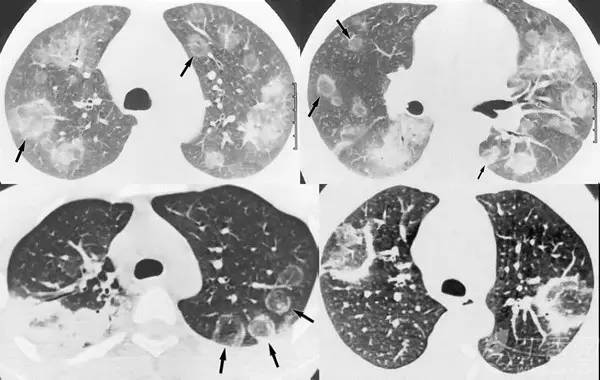

树芽征是指病变累及细支气管时,由于炎性渗出物或分泌物堵塞细支气管,CT 表现为小叶中心分枝状线影和与其相连的细支气管横断面结节影,状如春天里挂满枝芽的「树」,即「树芽征」。

CT 不能显示直径小于 2 mm 支气管,故正常小叶支气管 CT 扫描时不显示,但当小叶支气管发生病变时,CT 就可以显示出来。

树芽征的相关疾病有:肺支气管的感染性病变、免疫性疾病如变应性支气管肺型曲霉菌病、先天性疾病如囊性肺纤维化及纤毛运动异常综合征(Dyskinetic’s 综合征)、吸人刺激性物质等。